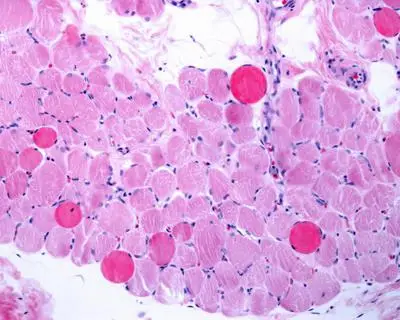

Malattie rare, risultati positivi a 5 anni per vamorolone in distrofia Duchenne